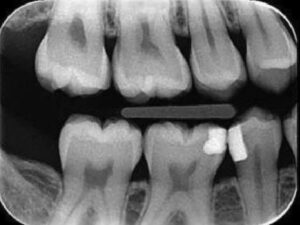

- Desgaste anormal del esmalte dental

- Sensibilidad dental o fisuras en las piezas

- Fracturas dentales o restauraciones dañadas

- Pérdida de la dimensión vertical de oclusión